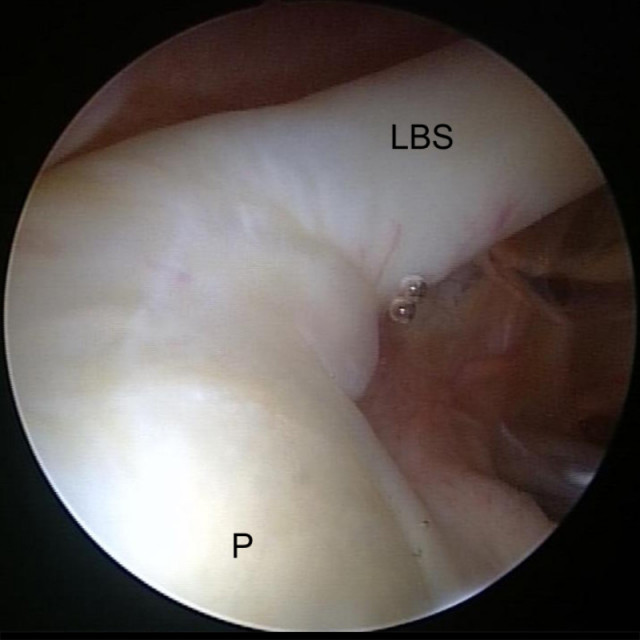

Gesunde Schulter mit normalem Abgang

Gesunde Schulter mit normalem Abgang der langen Bizepssehne (LBS) von der Pfanne (P)

Sie umschließen teilweise den Ausgang der Bizepssehne aus dem Gelenk und bilden zusammen mit einigen Verstärkungsbändern den sogenannten Bizeps-Pulley. Dieser stabilisiert die lange Bizepssehne.